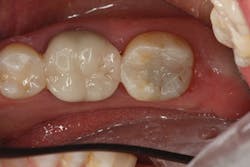

The contouring and primary anatomy can be placed with a flame-shaped fine diamond. Next, the occlusion is checked and refined on the restoration. Finally, the restoration can be polished easily with a two-step technique. I like to use polishing cups so I can polish both the occlusal and interproximal without having to change to a different polishing point. I first use Enhance (Dentsply Sirona), which can help shape as it polishes, and the final high shine is placed with the PoGo cup (Dentsply Sirona; figure 4).